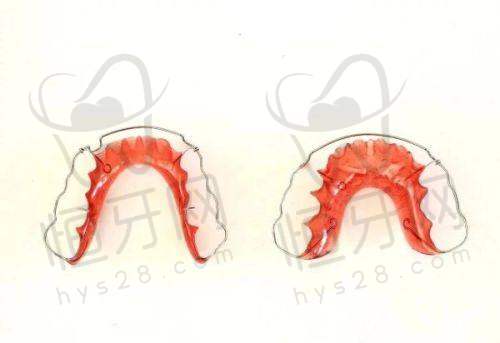

福州晨洁口腔医院在微创拔牙、儿童早期矫治方面口碑良好,服务体验优。

特色亮点:微创拔牙能减少患者的痛苦,儿童早期矫治可以在孩子牙齿发育的关键时期进行干预,让牙齿排列更整齐。优质的服务体验也能让患者在治疗过程中感受到温暖。